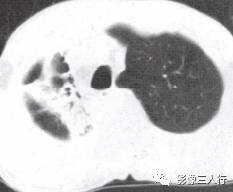

由于实变的肺组织与含气的支气管相衬托,在实变区中可见透明的支气管影即空气 支气管征,临床常见于大叶性肺炎的实变期,包括红色肝样变及灰色肝样变期,表现为密度均匀的致密影内可见透明的支气管影(图1)。这一征象被认为是肺泡炎性病变的有力证据。 医学百科网 | YxBaike.Com